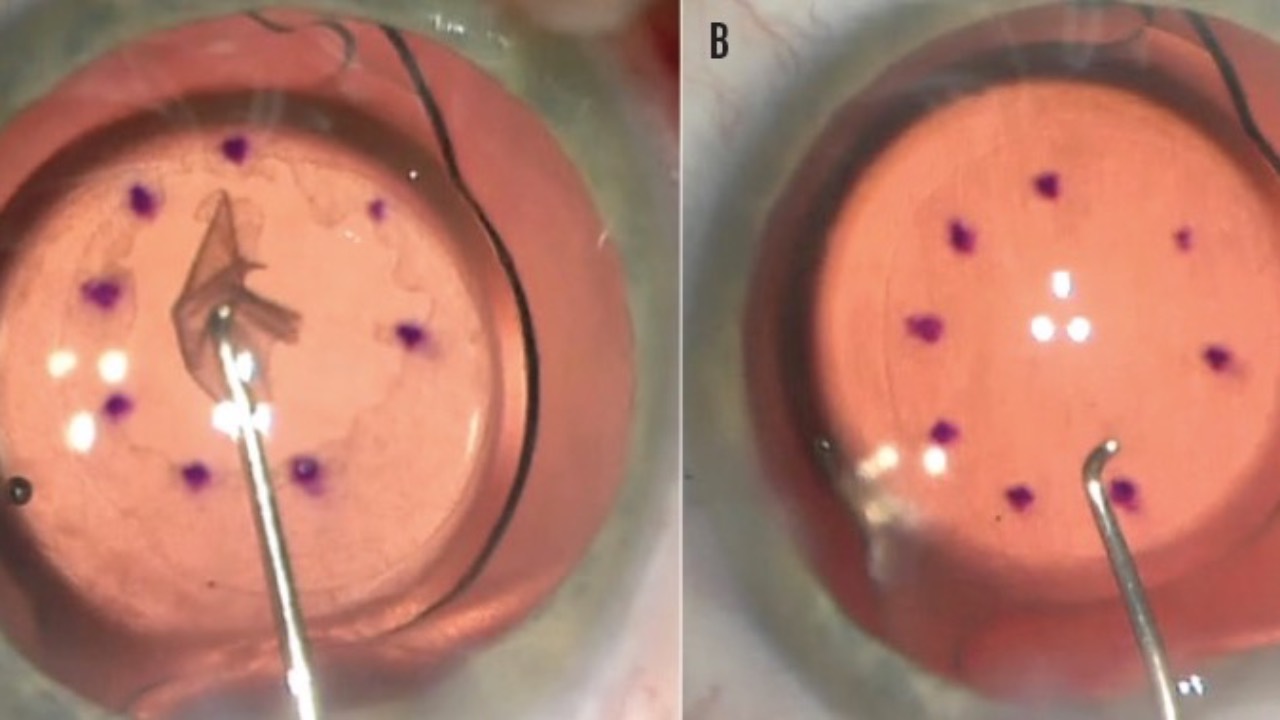

Fuchs Corneal Dystrophy & Ready For Surgery

Your patient asks you what's best. What do you say?...

Ten-year outcomes in corneal transplantation techniques have yielded important insights to help us advise individuals with Fuchs endothelial corneal dystrophy who are considering surgery. Surprisingly, penetrating keratoplasty (PK) demonstra...